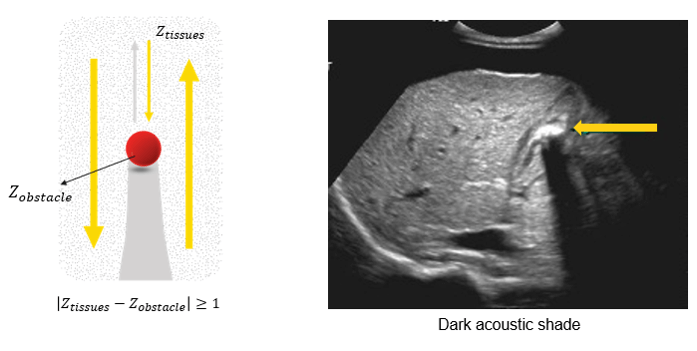

The greater the difference in acoustic impedance between two adjacent tissues, the more ultrasound energy will be reflected at the boundary. The acoustic shadow occurs when the sound wave meets a very dense structure. Almost all the sound is reflected, resulting in an acoustic shadow. Shading can occur due to intense reflectors such as calcification, air, or bone.

Acoustic Shade

The acoustic shadow phenomenon occurs whenever the ultrasonic beam is intercepted by a highly reflective structure. This is the case of bones, digestive gases, kidney stones, or gallstones. In this image, the reflecting wall is represented by a very intense echo behind, which is projected in a cone of acoustic shadow where no image is visible. This artifact aids in the identification of calculi and also prevents the examination of deeper structures.